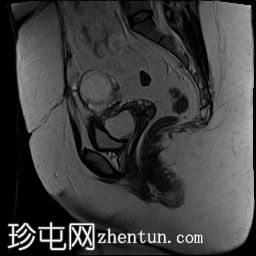

MRI

6.jpg

矢状面

T2

子宫下段前壁变薄,存在约 5 毫米的小缺损/裂开,并从中突出一个大囊性病变/憩室,与子宫内膜腔相通。它在 T1WI 和 T2 WI 上显示高强度信号,在 T1FS 上没有信号下降,表示有出血信号。发现结果与先前子宫下段手术疤痕处的子宫龛裂开一致,憩室(峡部膨出)含有出血内容物。

子宫大小正常,子宫内膜厚度正常,无明确局灶性病变。

左卵巢囊性病变显示内部分隔,在 T1WI 和 T1FS WI 上呈现低到高混合信号,在 T2WI 上呈现高信号,提示左卵巢出血性囊肿/子宫内膜异位症。囊肿后内侧可见消失的卵巢组织和卵泡。

右卵巢增大(17 cc),显示多个小卵泡液体信号。